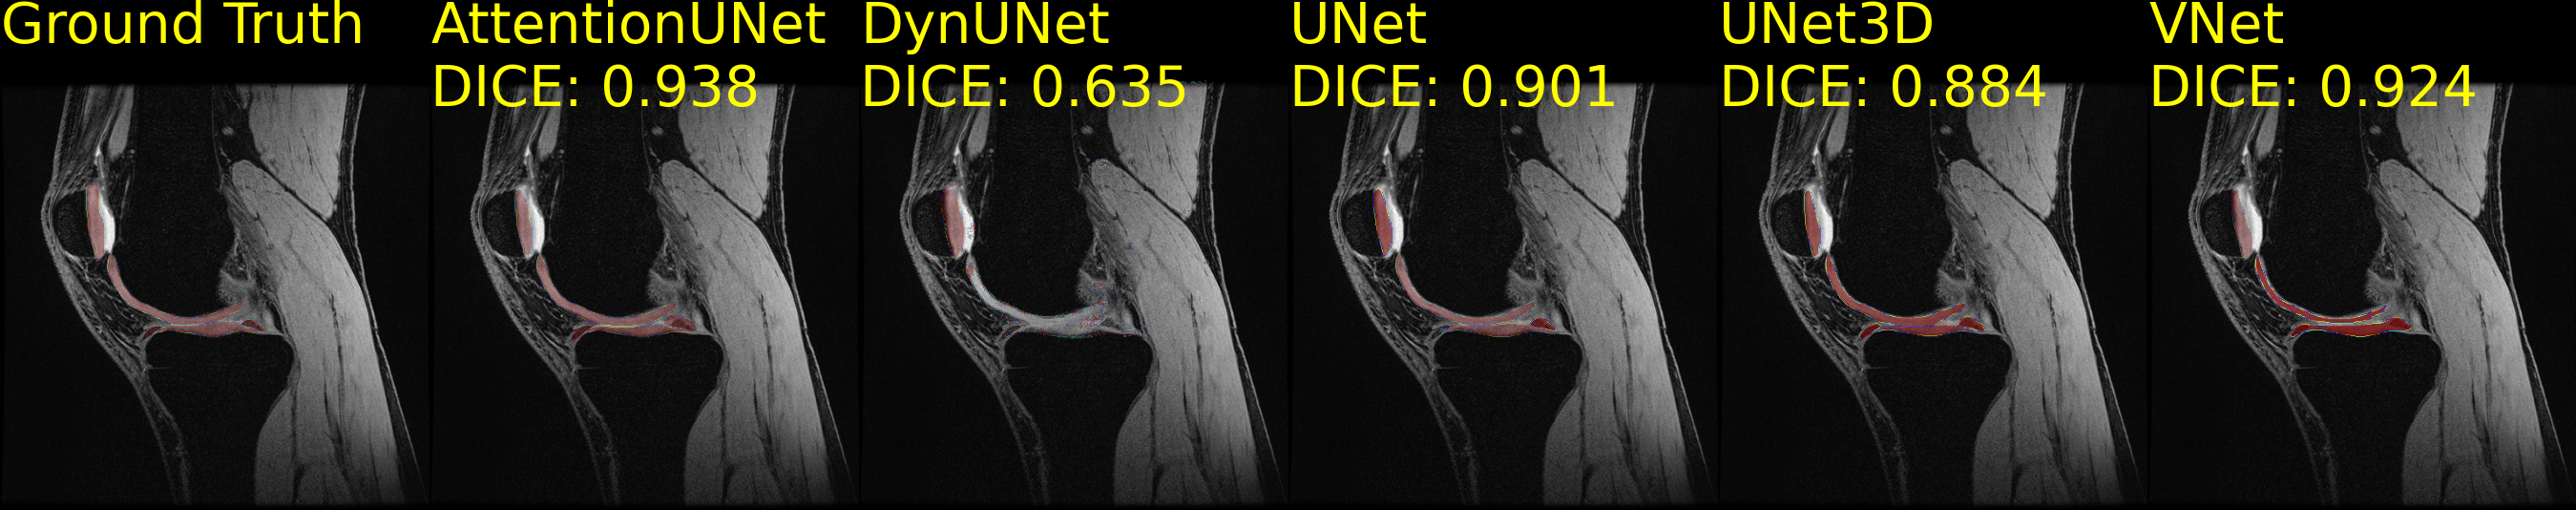

Table 5 presents the performance in the segmentation task of models trained on the BraTS2023AdultGlioma and the SKM-TEA segmentation-only datasets. On the BraTS2023AdultGlioma dataset, the UNet achieved the highest DICE score and the lowest HD95 score, while the UNet3D achieved the highest F1 score and the AttentionUNet the highest IOU. Although the high DICE scores, F1 and IOU scores were reported lower, which may be attributed to the heterogeneous tumors, leading to the inclusion of non-tumor regions in the predicted segmentation. Similar observations were made on the SKM-TEA segmentation-only dataset, where the UNet3D and VNet achieved the highest DICE score. While the UNet3D scored the highest IOU, the VNet scored the lowest HD95 and the highest F1. In general, the lower F1 scores may be attributed to the heterogeneity of the data since they were acquired from multiple vendors (Sec. 3.5.1). The variability of knee structures across different patients could cause low IOU scores. The impact on the variability between high DICE scores and low F1 and IOU scores can be seen in Fig. 9(a) and Fig. 9(b), where the DynUNet underestimated the segmented classes, resulting on the worst-performing model.

Refer to caption

(a) Brain Tumor Segmentation 2023 Adult Glioma segmentations.

(b) Stanford Knee MRI with Multi-Task Evaluation segmentations.

(c) ISLES 2022 Sub Acute Stroke segmentations.

Figure 9: Segmentations on the Brain Tumor Segmentation 2023 Adult Glioma dataset (Fig. 9(a)), the Stanford Knee MRI with Multi-Task Evaluation (SKM-TEA) segmentation-only dataset (Fig. 9(b)), and the ISLES 2022 Sub Acute Stroke dataset (Fig. 9(c)). The first image on each figure shows the Ground Truth image with the segmentation labels. The rest of the images present the segmentations of different methods. Each segmentation method’s DICE score is reported and computed against the Ground Truth labels. Methods are sorted alphabetically.